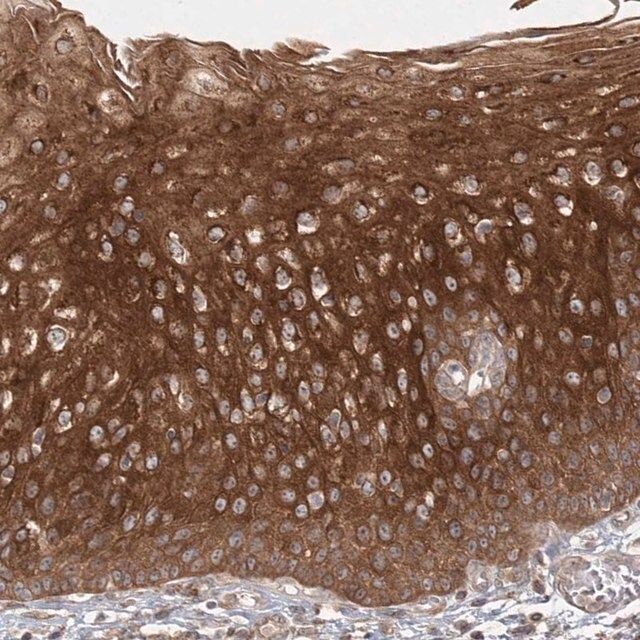

The Human Protein Atlas project can be subdivided into three efforts: Human Tissue Atlas, Cancer Atlas, and Human Cell Atlas. The antibodies that have been generated in support of the Tissue and Cancer Atlas projects have been tested by immunohistochemistry against hundreds of normal and disease tissues and through the recent efforts of the Human Cell Atlas project, many have been characterized by immunofluorescence to map the human proteome not only at the tissue level but now at the subcellular level. These images and the collection of this vast data set can be viewed on the Human Protein Atlas (HPA) site by clicking on the Image Gallery link. To view these protocols and other useful information about Prestige Antibodies and the HPA, visit sigma.com/prestige.

- IHC tissue array of 44 normal human tissues and 20 of the most common cancer type tissues.